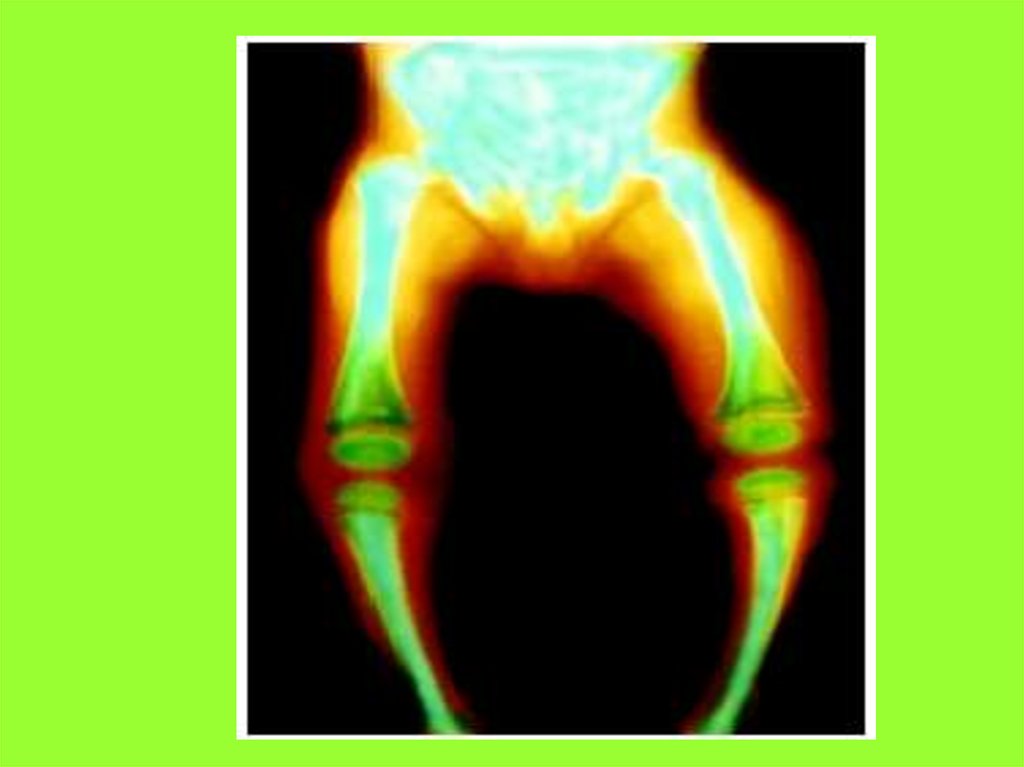

Подавляющее количество витамина D образуется в

коже, под действием солнечных лучей.

Незначительная часть витамина попадает

в организм с пищей через желудочно-кишечный

тракт. В обоих случаях, витамин D

поступает в организм в неактивной форме.

Перед тем, как осуществить свою главную роль,

он активируется в печени и почках.

Витамин D действует на уровне двух систем:

• в просвете кишечника помогает всасыванию

кальция и транспортировке его в кровь;

• на уровне почек уменьшает выведение кальция

и фосфора с мочой.